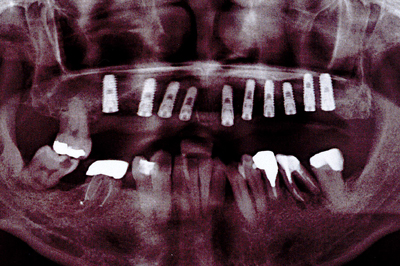

治療例1

| ご費用 | 手術費用人工歯根 1本275,000円(税込) 上部構造 88,000円~110,000円(税込) |

|---|---|

| リスク・副作用 |

保険非適応(自費診療) 特定の全身疾患や持病のある方、顎骨密度の足りない方、妊娠中の方は手術ができない場合があります。 下顎のインプラント手術の際、偶発症のリスクがあります。 人工歯根が顎骨と癒着しないリスクがあります。 インプラント周囲炎になるリスクがあります。 |